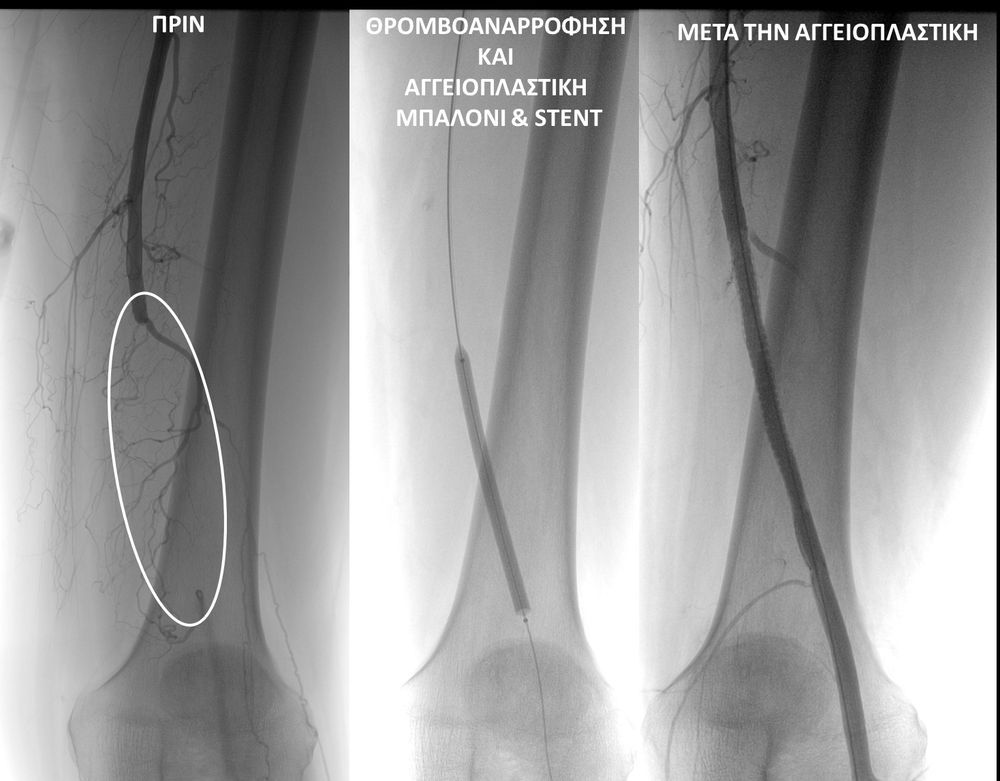

Κλασική χειρουργική αντιμετώπιση (ανοιχτή προσπέλαση) ή αγγειοπλαστική με τοποθέτηση Stent (ενδοαγγειακή προσπέλαση) -γνωστή στο ευρύ κοινό ως τεχνική μπαλονάκι